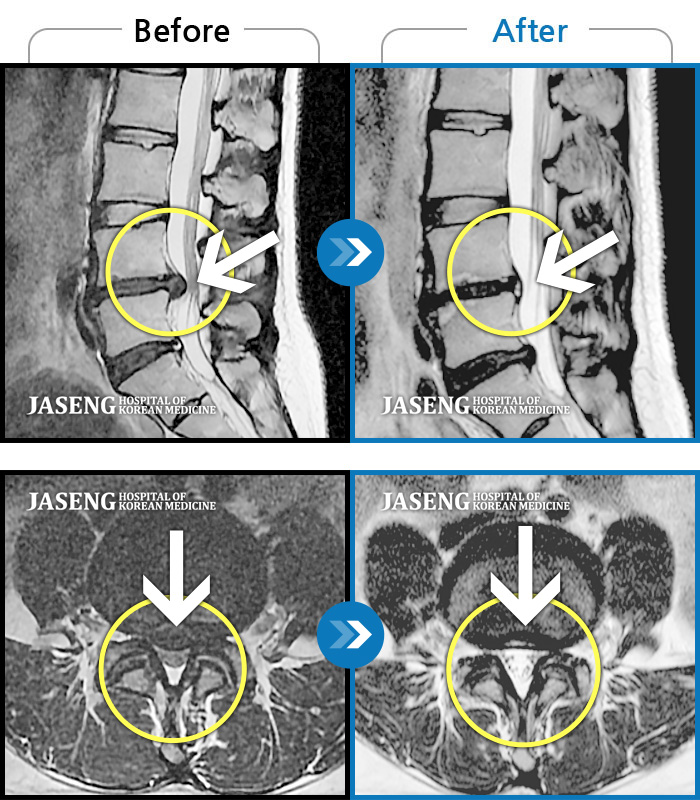

MRI 치료사례

허리통증, 오른쪽 다리 저림 및 통증